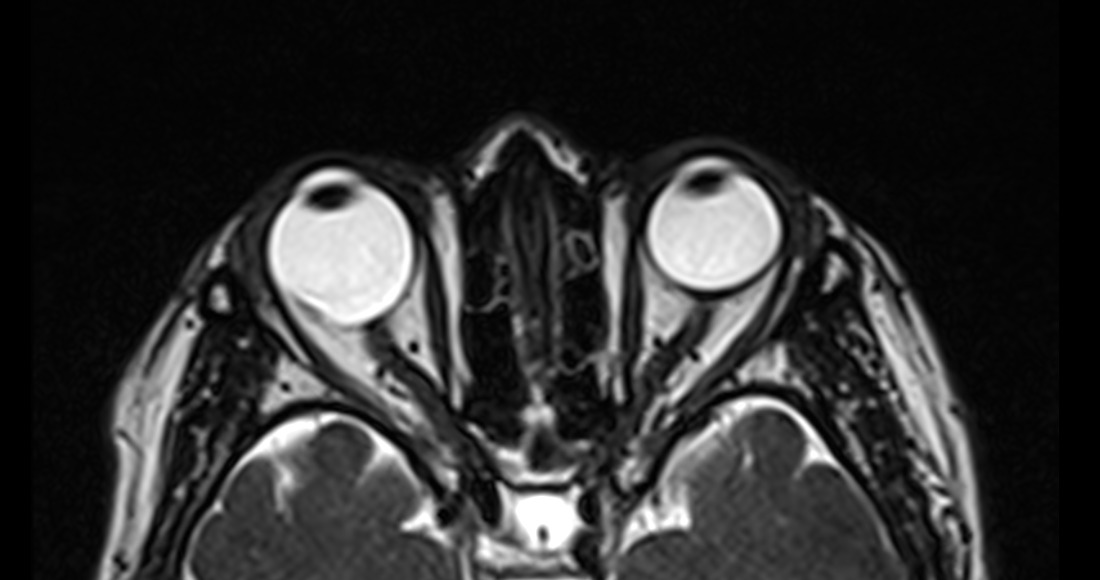

Cortes axiales de resonancia magnética de órbitas en el cual se aprecia aumento del tamaño del globo ocular derecho a expensas de su eje anteroposterior, acompañado de adelgazamiento de su pared posterior lo cual corresponde a estafiloma.

Definición: Adelgazamiento y estiramiento de las capas escleral-uveal del globo ocular.

Hallazgos por imagen: Aumento del tamaño del globo ocular y adelgazamiento de sus paredes posteriores.